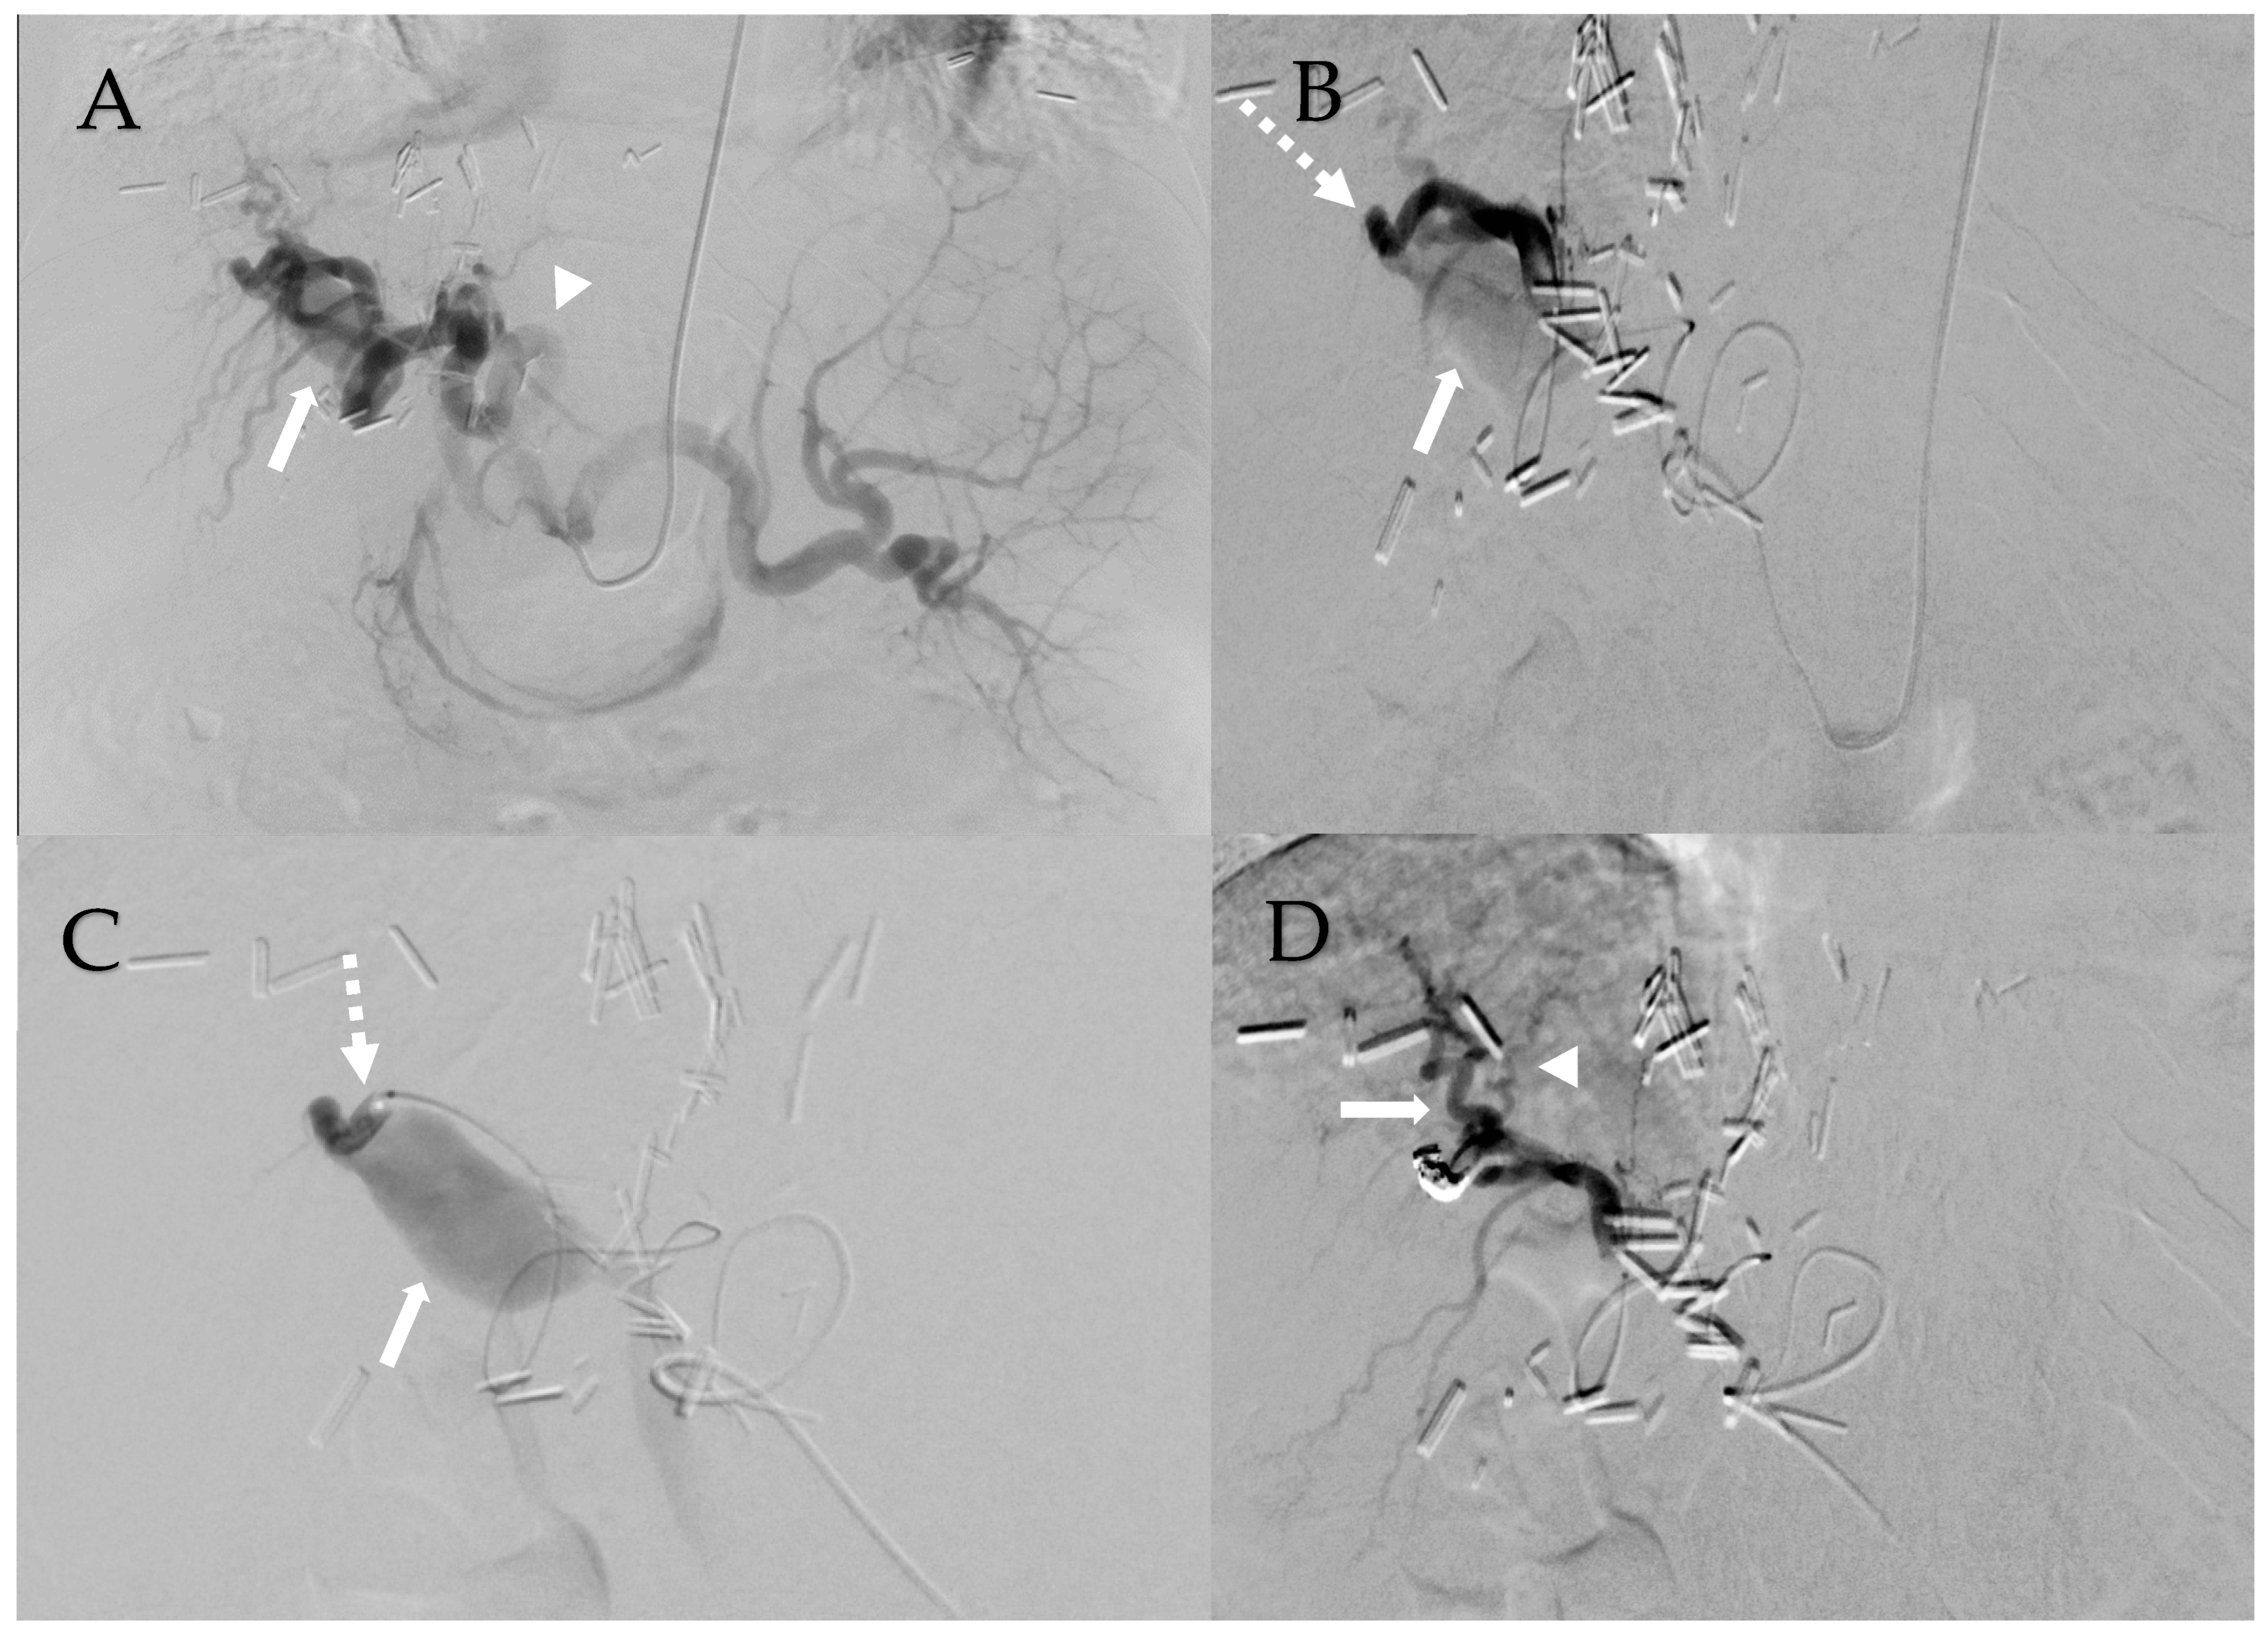

Given the extensive nature of the HAPVF and his hepatic decompensation, the decision was made to treat the fistula with transcatheter embolization. His pre-operative lab work included a creatinine of 1.6 mg/dL, total bilirubin 1.48 mg/dL, platelets 51,000, and INR 1.35. Celiac arteriography revealed a dilated and extremely long and tortuous common and proper hepatic artery (Figure 2A). Hepatic arteriograms demonstrated a short-segment fistula between the right hepatic artery and the portal vein (Figure 2B,C). Close and central to the fistula were two significant branches of the right hepatic artery. Attempts were made to deploy a vascular plug into the fistula without success because the delivery sheath could not track along the tortuous hepatic artery. The initial placement of detachable coils resulted in unconstrained extension into the main portal vein, requiring their removal before deployment. Finally, detachable coils were deployed into the short-segment fistula (one Concerto 2 mm and one Concerto 8 mm coil). A post-embolization arteriogram showed occlusion of the HAPVF without injury to the two adjacent normal right hepatic arteries (Figure 2D). His bilirubin decreased from 1.48 to 1.02 mg/dL. Post-procedure MRI found successful closure of the HAPVF with patent hepatic arteries and portal vein without early enhancement, but rather with occlusion of the main, left, and right portal veins. There were periportal collaterals suggesting cavernous transformation. We presume that the hepatic artery had been providing retrograde flow into the portal system, which subsequently thrombosed after fistula closure. The splenic vein and superior mesenteric vein remained patent. A CT scan with contrast performed 4 years after embolization shows persisting portal vein thrombosis and the collateralization of portal venous inflow (Figure 3).

Figure 2. Management of hepatic arterio-portal venous fistula. (A): Celiac axis arteriogram shows hypertrophied and tortuous common/proper hepatic arteries (arrowhead) and bulbous portal vein (arrow). (B): Right hepatic artery arteriogram shows tortuous hepatic arteries with short-segment hepatic artery fistula (dashed arrow) with immediate opacification of the portal vein (arrow). (C): Right hepatic artery arteriogram shows short-segment hepatic artery fistula (dashed arrow) with immediate opacification of the portal vein (arrow). (D): Right hepatic artery arteriogram status post coil embolization of short-segment fistula shows two adjacent right hepatic arteries that remain patent (arrow, arrowhead). Portal vein is no longer appreciated.